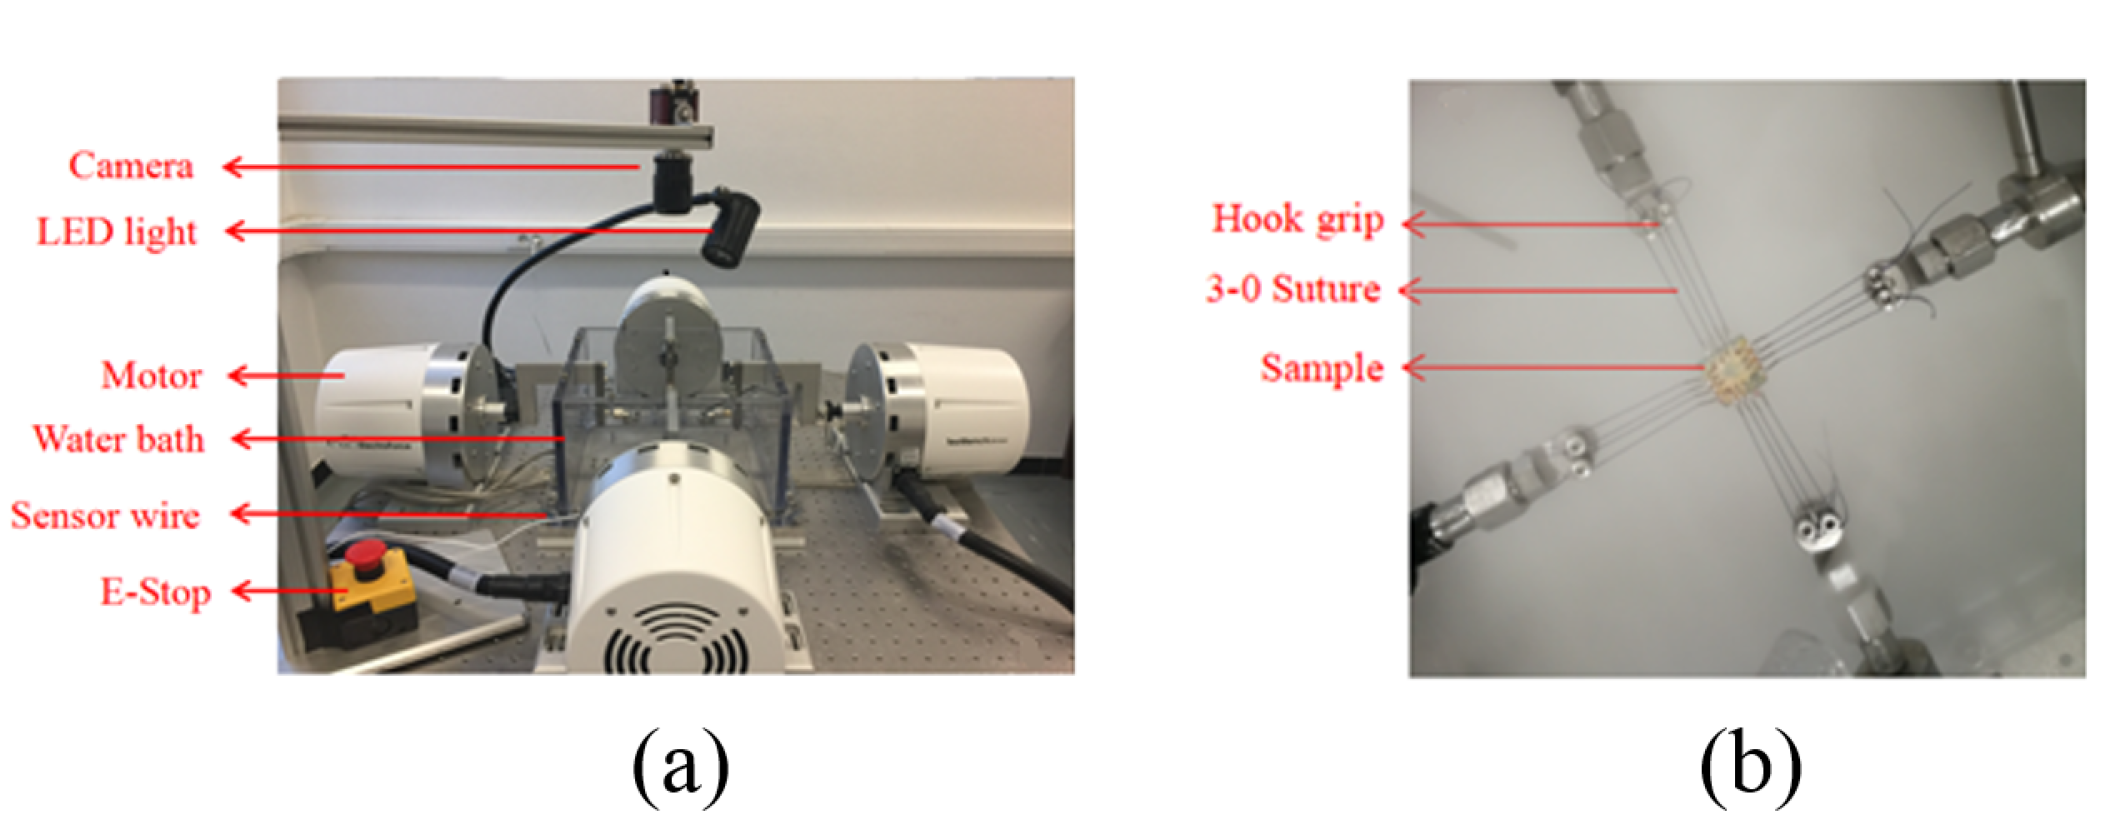

2.3.2. Ex-Vivo Data